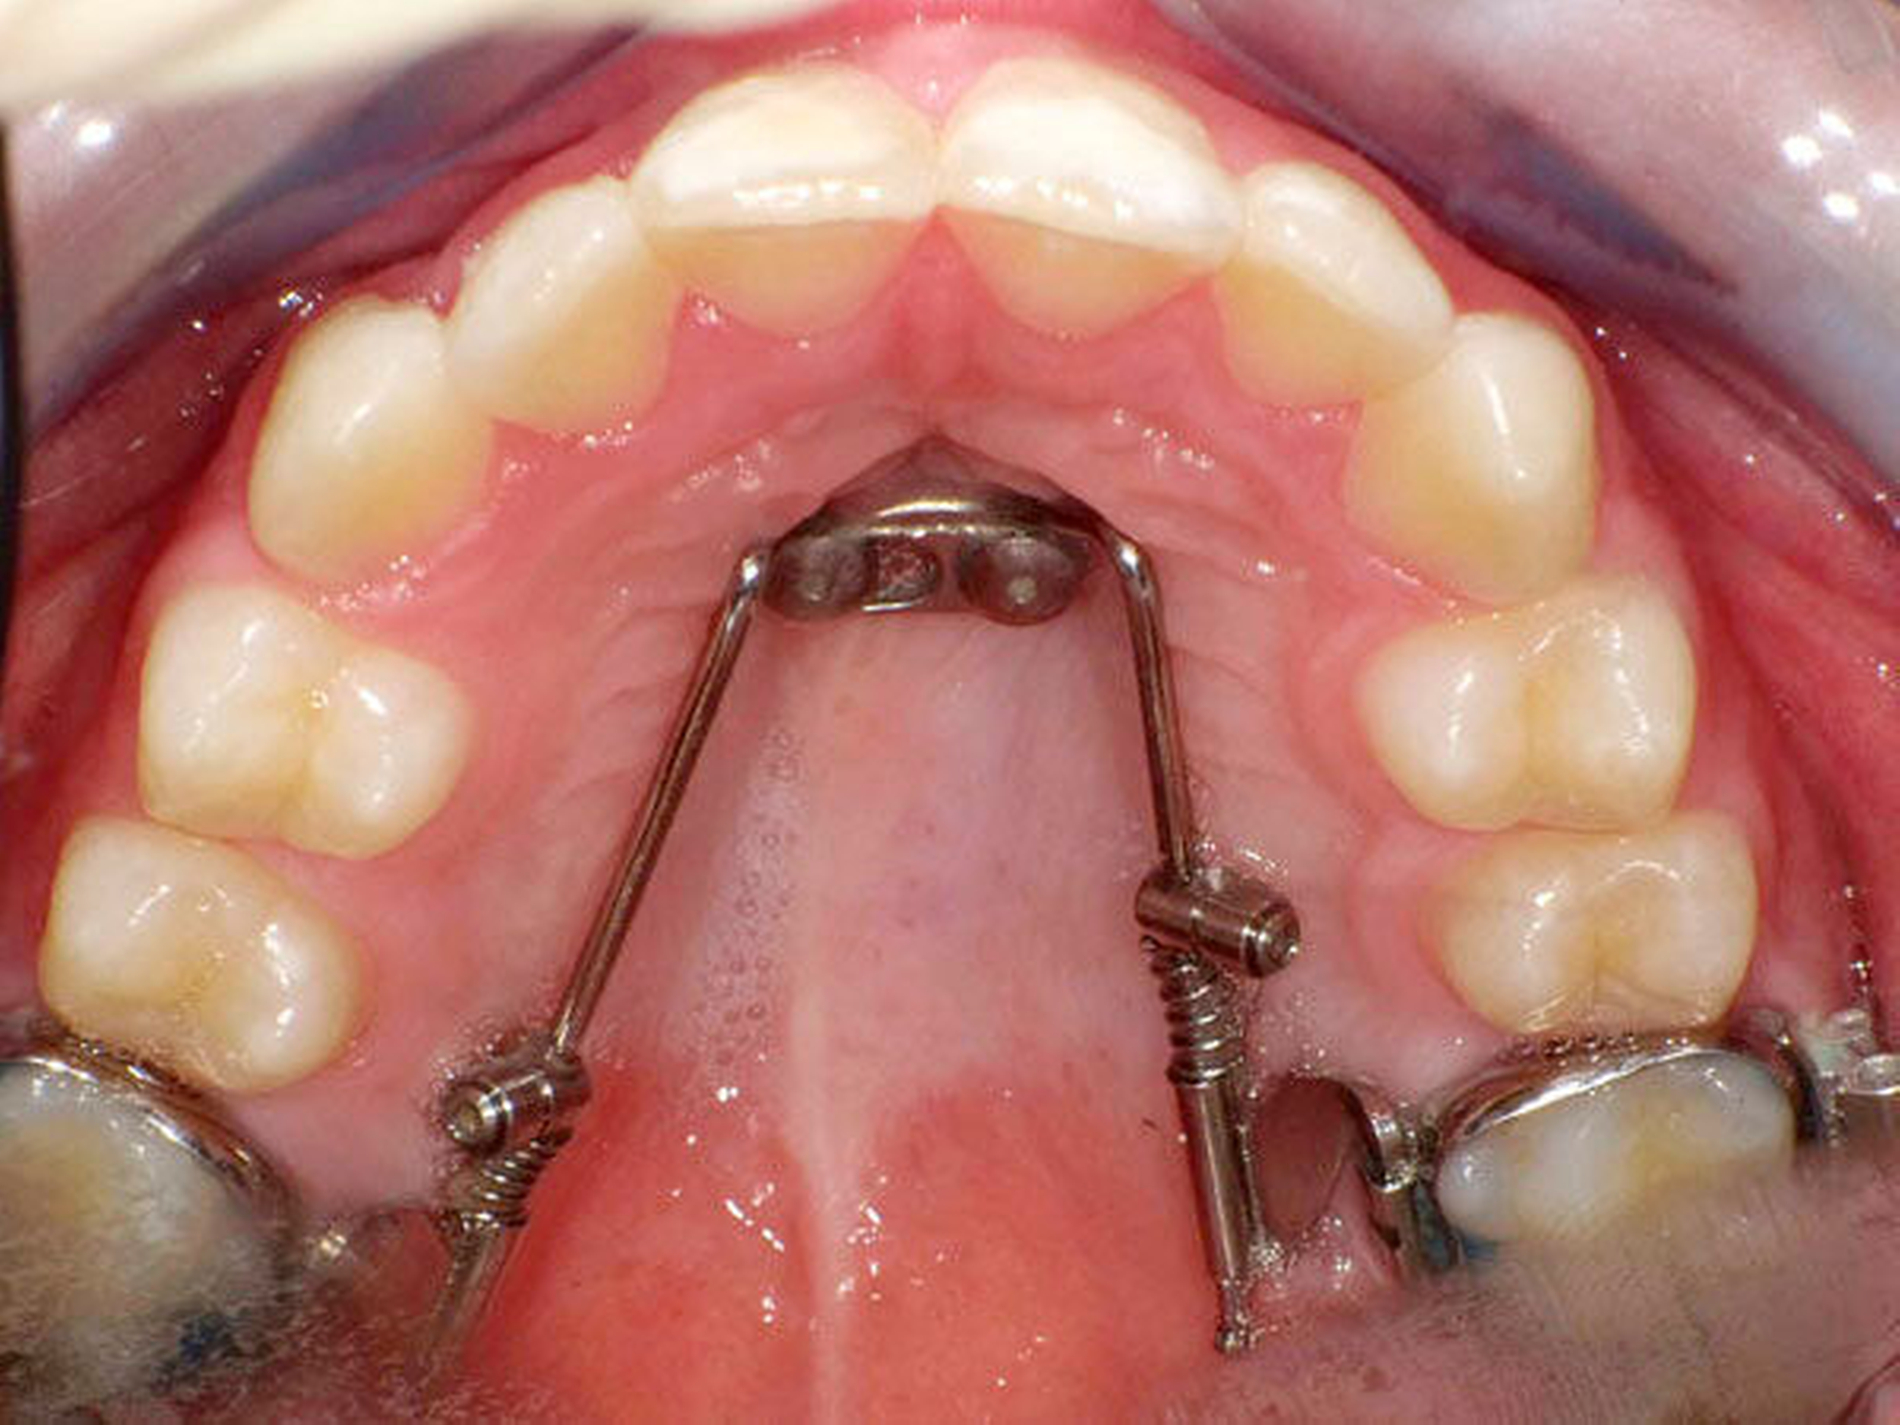

Das Prinzip einer CAD/CAM-gesteuerten Insertion wird anhand einer zehnjährigen Patientin mit einem Platzmangel für die oberen Eckzähne dargestellt (Abbildungen 4a, 4b). Die Behandlung begann mit dem Anpassen von Molarenbändern und einem Silikon-Abdruck des Oberkiefers, der mit dem FRS an das zahntechnische Labor gesendet wurde und dort mit dem FRS der Patientin überlagert wurde. So konnten geeignete Insertionsstellen virtuell geplant werden (Abbildungen 1, 2a, 2b). Nach Rücksprache mit dem Behandler bezüglich der Mini-Implantatpositionen erfolgte die Herstellung der Insertionsschablone (Abbildung 3). Parallel dazu wurde auch der Beneslider [Wilmes, 2010] hergestellt, der zusammen mit der Insertionsschablone geliefert wurde (Abbildung 5). Mithilfe der Insertionsschablone konnten die Mini-Implantate und der Beneslider im selben Termin eingesetzt werden (Abbildungen 6, 7a, 7b). Nach 10 Monaten Distalisierung waren die Molaren in der Zielposition und es war ausreichend Platz für die Eckzähne vorhanden (Abbildungen 8a, 8b), so dass Brackets für die zweite Phase der Behandlung eingesetzt werden konnten. Die Multibracket-Apparatur (Abbildung 9) konnte nach 12 Monaten entfernt werden (Abbildungen 10, 11).